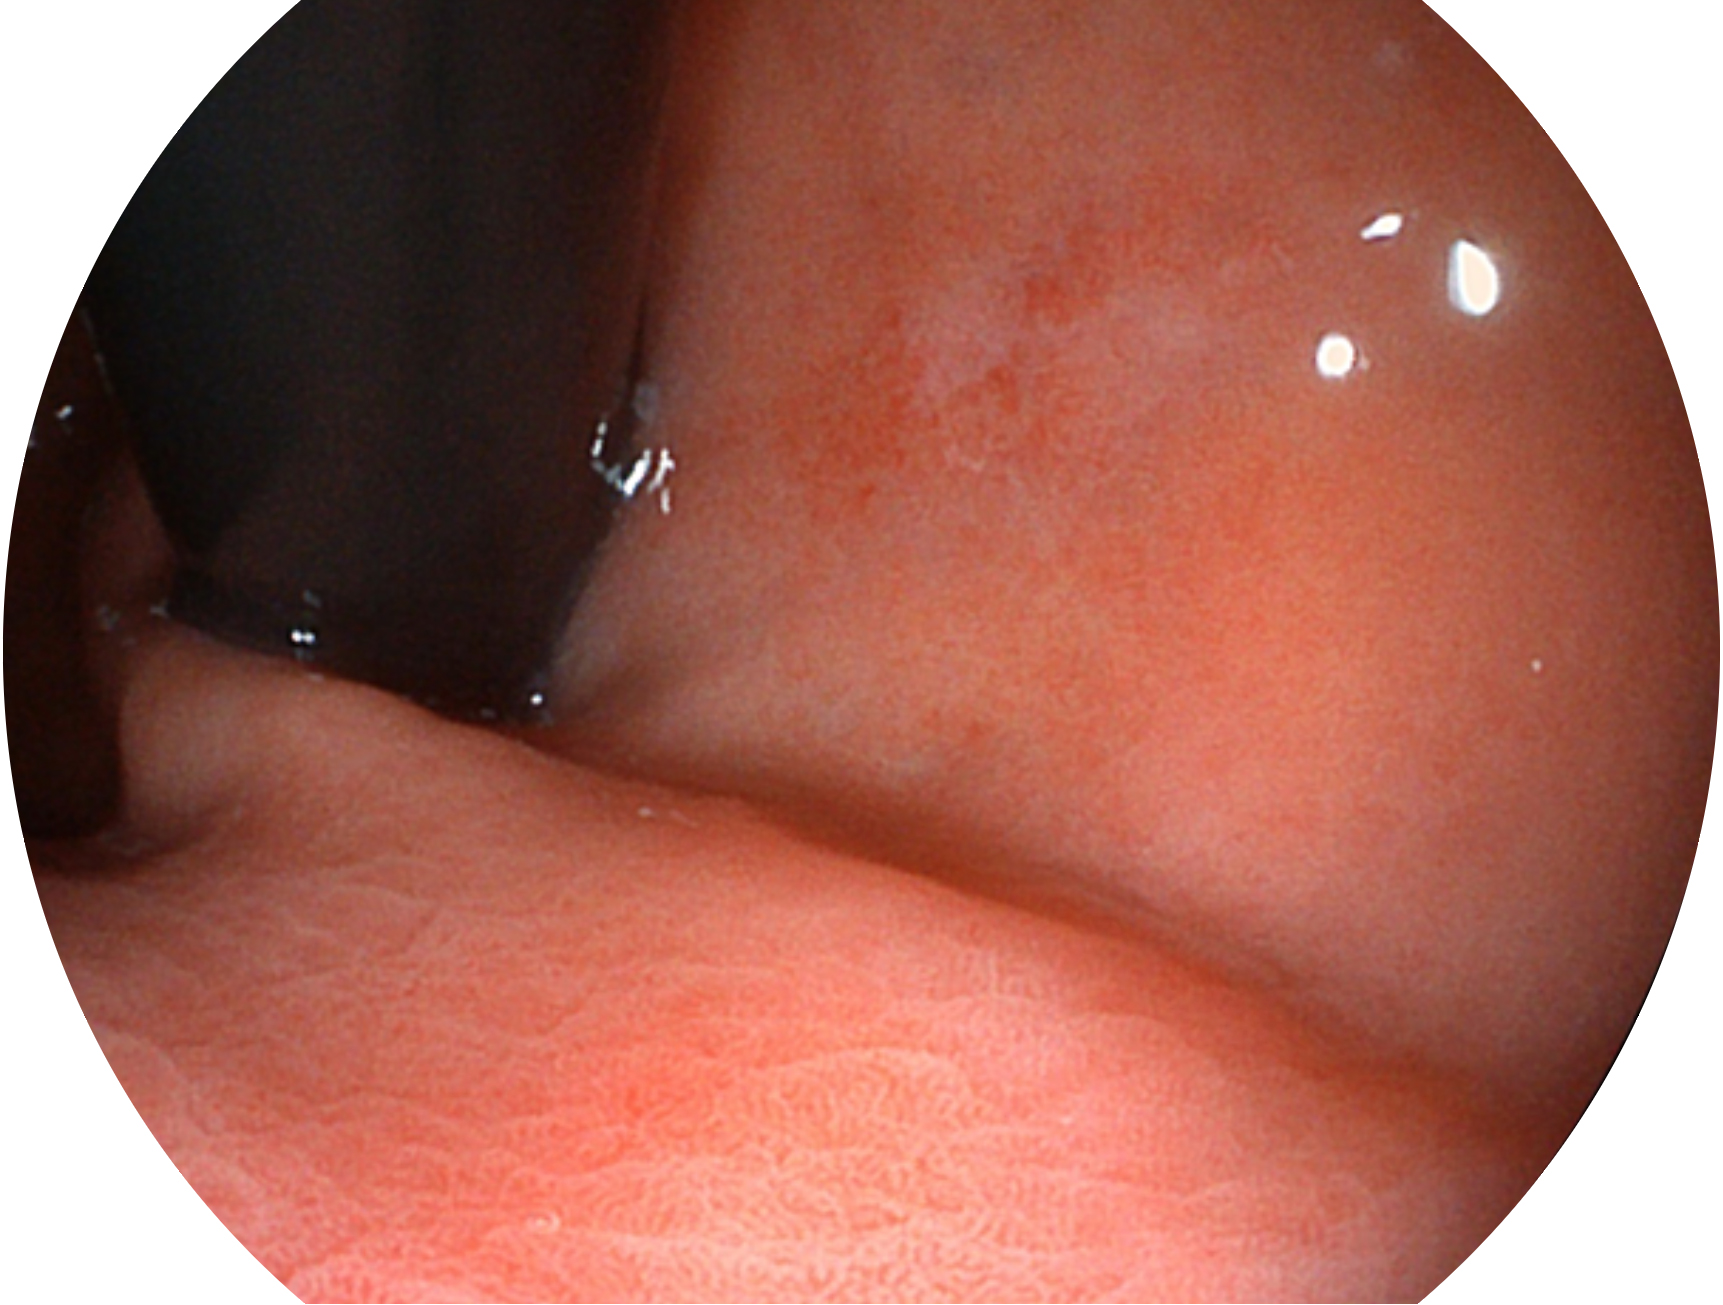

milan米兰新开发的内镜染色技术,主要是基于多波长LED 光源的开发,VLS-55Q 四波长LED 光源是由四个不同颜色的LED光按照相应照明模式所规定的特定发光比例进行合束后形成,合束后形成的照明光的光谱由红光、绿光、蓝光及蓝紫光这四个不同的波段范围构成。具有更高光谱自由度,通过光谱比例的控制,实现了聚谱成像技术,英文全称为“Spectral Focused Imaging, SFI”,缩写为“SFI”和光电复合染色成像技术,英文全称为“Versatile Intelligent Staining Technology, VIST”,缩写为“VIST”。